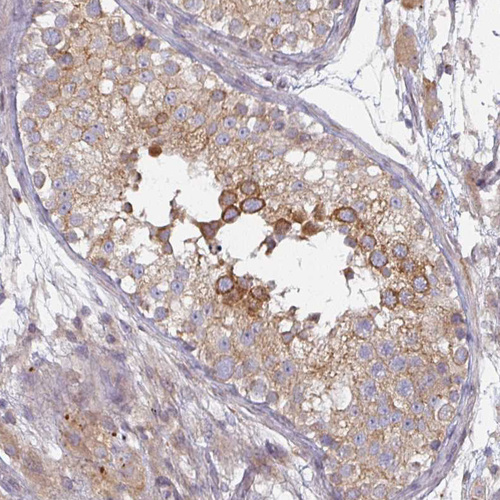

Immunohistochemical staining of human liver shows moderate cytoplasmic positivity in hepatocytes.